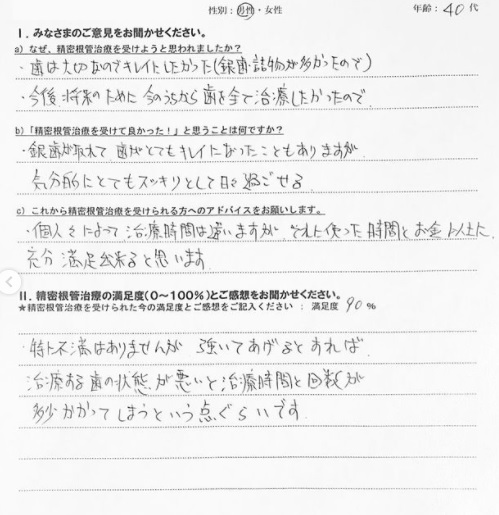

【患者様の声】精密根管治療を受けた40代男性の方です

こんにちは! 南館歯科クリニックの歯科衛生士 山崎です。 精密根管治療を受けた方の声をご紹介します。 綺麗になって気分もスッキリなんてとても素敵ですね👏 清々しい日々を送れている様で嬉…